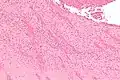

Intermediate magnification micrograph showing laminations in a thrombus in a fatal pulmonary embolism. H&E stain.